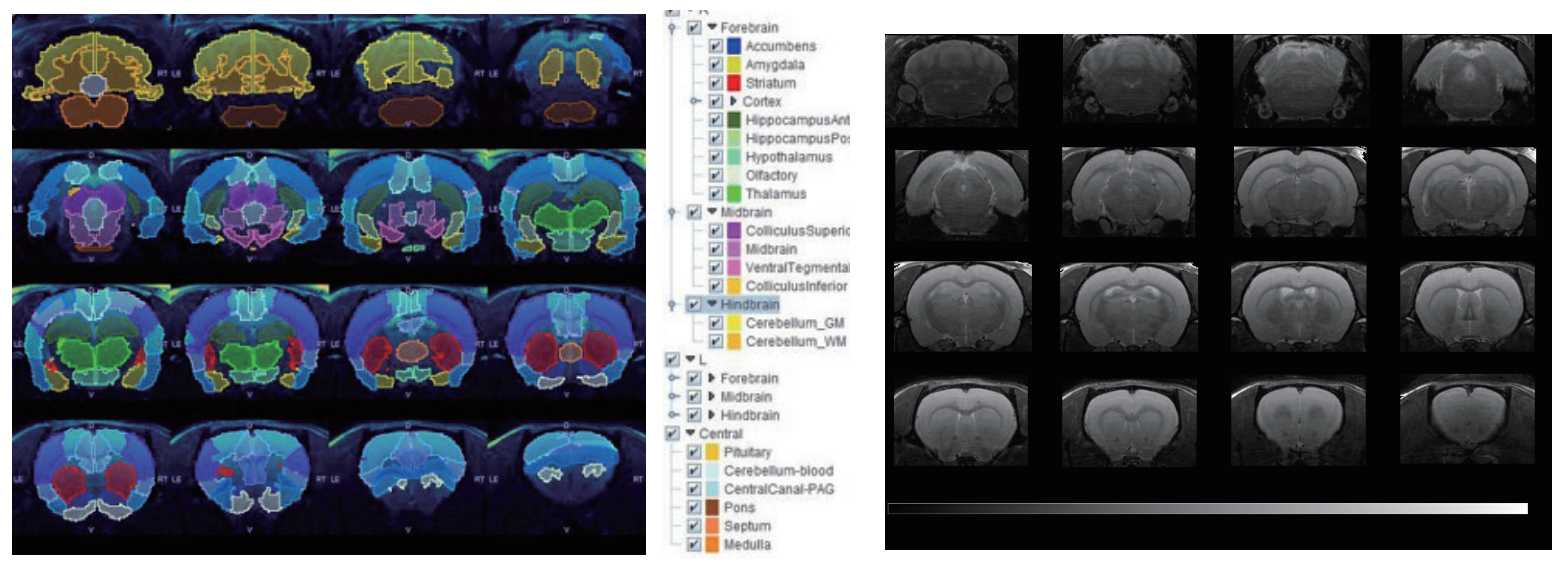

7T磁共振下大鼠脑部RARE影像,使用PMOD软件分割。